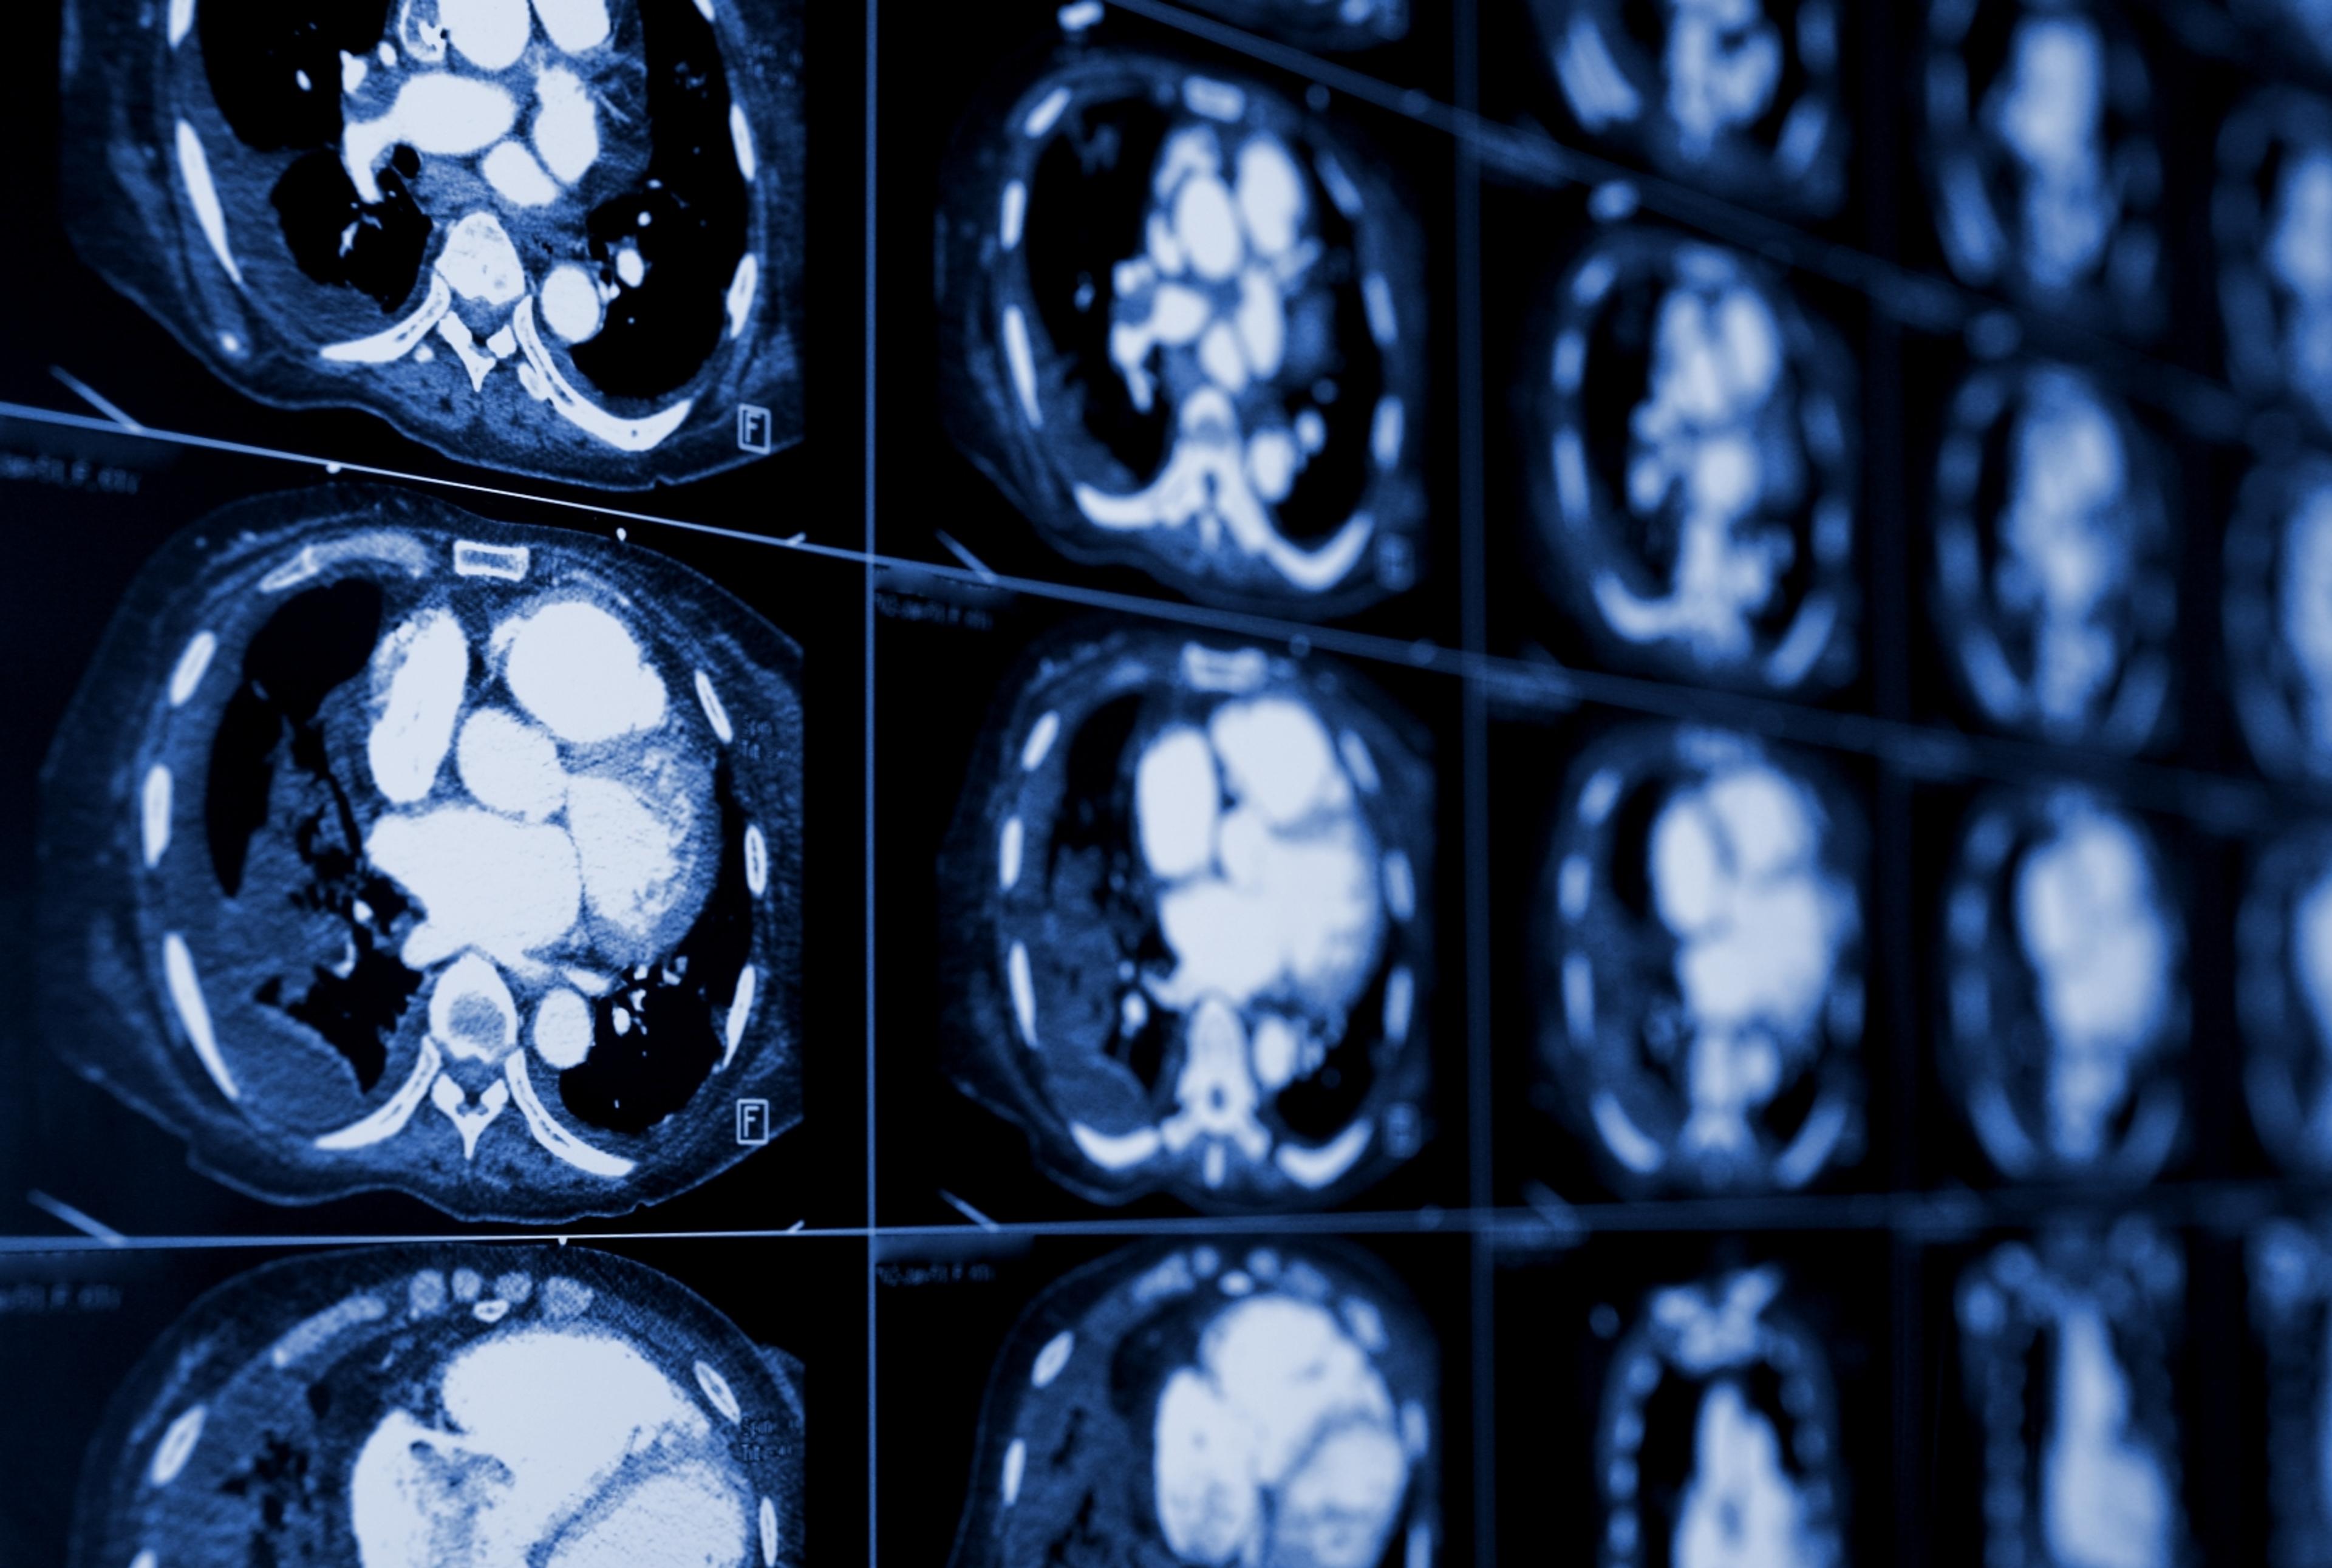

CT scanning joins specialized x-ray equipment with a computer to produce multiple images or pictures of the inside of the body. The images are joined together in cross-sectional views of the area studied, then examined on a computer monitor or printed.